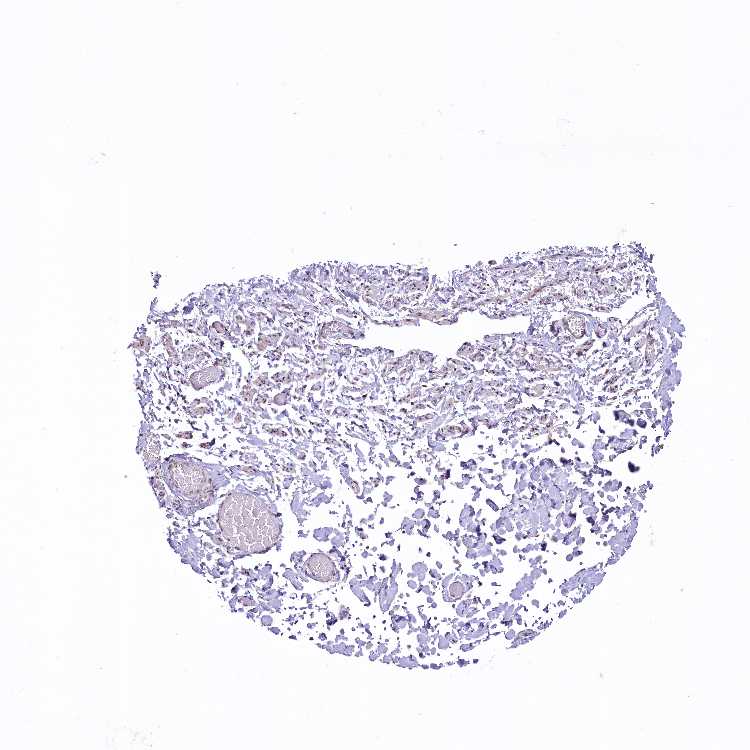

SOFT TISSUE 1 - Antibody stainingi

Antibody staining in the annotated cell types in the current human tissue is reported as not detected, low, medium, or high, based on conventional immunohistochemistry profiling in selected tissues. This score is based on the combination of the staining intensity and fraction of stained cells.

Each image is clickable and will lead to virtual microscopy that enables deeper exploration of all samples and also displays staining intensity scores, fraction scores and subcellular localization as well as patient and tissue information for each sample.

Antibody HPA041409Antibody HPA041482

Chondrocytes -Low

Fibroblasts MediumNot detected

Peripheral nerve MediumNot detected